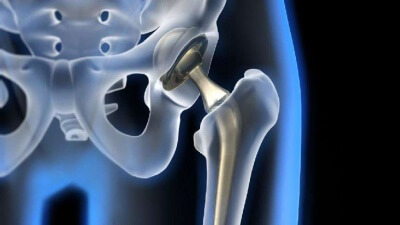

Опыт применения остеопластических материалов при ревизионном эндопротезировании тазобедренного сустава

ТРАВМАТОЛОГИЯ